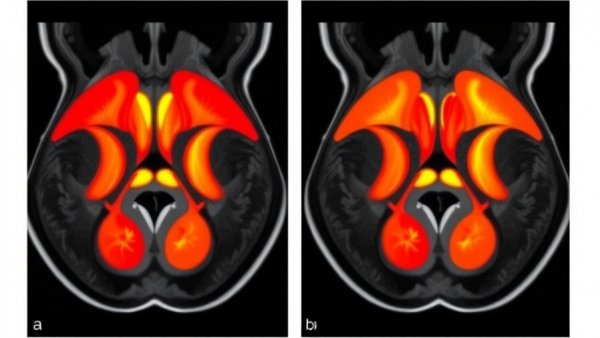

Comprehensive quantitative analysis of muscle cross-sectional area and intramuscular fat infiltration of hip using modified DIXON MRI based on chemical shift encoding technique

The recent study utilizing the modified DIXON MRI technique has brought significant insights into the relationship between muscle cross-sectional area (CSA) and intramuscular fat infiltration (IMFF) in the hip region. For health-conscious individuals, particularly those aged 30-55, understanding these factors is critical as they play a pivotal role in maintaining mobility and overall health.

The adoption of modified DIXON MRI allows for a noninvasive approach to quantitatively assess hip musculature. Unlike traditional methods, which involve more invasive procedures, MRI provides the means to visualize muscle health without the risks associated with muscle biopsies. This advancement not only enhances our understanding of muscle mass and fat infiltration but also opens the door for proactive health monitoring as individuals age.

The study observed that with advancing age, there is a noted decrease in the CSA of hip muscles alongside an increase in IMFF. This correlation between age and muscle composition is especially relevant for individuals interested in anti-aging strategies and cellular rejuvenation. Furthermore, the findings revealed significant sex differences; males exhibited a larger CSA and lower IMFF compared to females, indicating that hormonal factors may also play a role in muscle health.